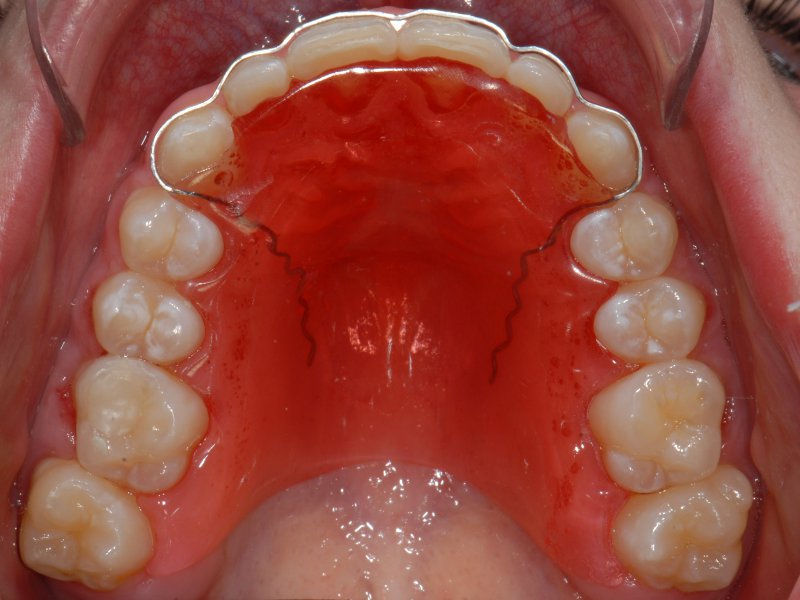

Retentionsplåt med tungavvisare